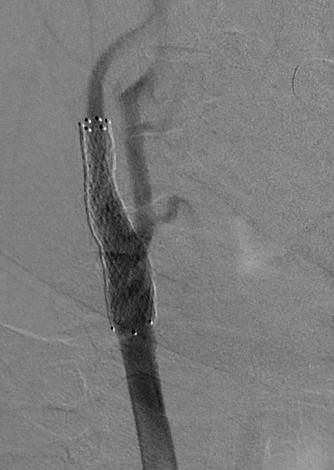

62-летний пациент жаловался на частые головные боли, головокружение и появление «мушек» перед глазами. Врачи провели ряд обследований и выявили критическое сужение (на 90%) правой внутренней сонной артерии. Было принято решение в кратчайшие сроки провести операции по установке стента для восстановления нормального кровотока.

После успешного лечения и контрольного обследования не было выявлено никаких нарушений кровообращения. Пациента выписали в удовлетворительном состоянии.